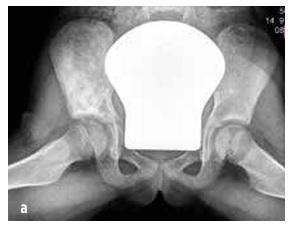

Maligne novotvorine

Kod djece najčešći su osteosarkom (55%, vidi Sliku 5) i Ewingov sarkom (35%, vidi Sliku 6), dok je hondrosarkom izuzetno rijedak. U ovu skupinu također spadaju sarkomi mekih tkiva (rabdomiosarkom i neralabdomiosarkomi), mesenchimski stanični tumori, ekstraskeletni Ewingov sarkom, sinovijalni sarkom, fibrosarkom i embrionalni sarkom.

Slika 6

Ewingov sarkom koji zahvaća zdjelični kostur